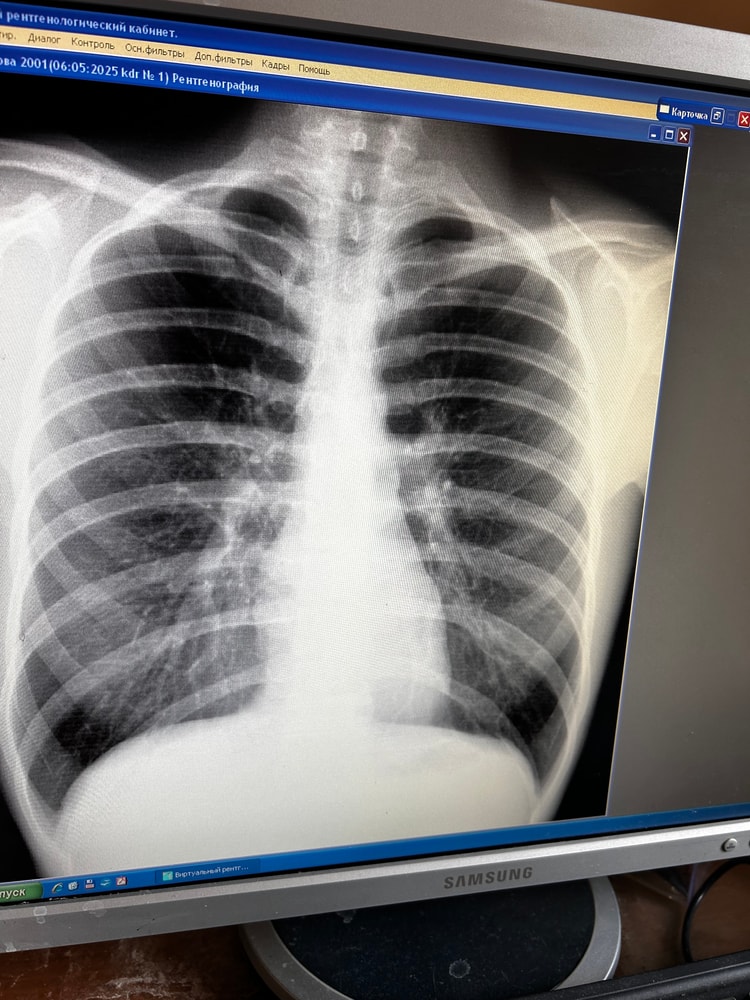

Сильно тревожат боли в грудиной клетке ,кашель не проходящий ,першение в горле ,потеря веса,поэтому дали направление на флг и кт